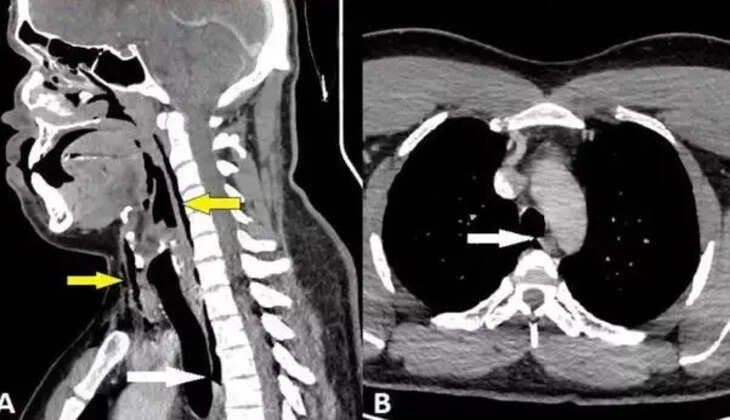

தோலின் ஆழமான திசு அடுக்குகளுக்குப் பின்னால் காற்று சிக்கிக்கொள்ளும் ஒரு நோயான அறுவைசிகிச்சை எம்பிஸிமா அந்த மனிதனுக்கு இருந்தது என்பது எக்ஸ்ரே மூலம் தெரியவந்தது. பின்னர், CT ஸ்கேன் பரிசோதனையில், அவரது கழுத்தின் மூன்றாவது மற்றும் நான்காவது முதுகெலும்புகளுக்கு இடையில் கிழிந்திருப்பது தெரியவந்தது. கூடுதலாக, அவரது நுரையீரல் மற்றும் அவரது மார்புக்கு இடையே உள்ள பகுதியில் காற்று கூடியிருந்தது. "மூக்கு மற்றும் மூடிய வாயுடன் தும்மும்போது மூச்சுக்குழாயில் விரைவான அழுத்தம் அதிகரிப்பதால்" சேதம் ஏற்பட்டது என்று மருத்துவ நிபுணர்கள் முடிவு செய்தனர்.